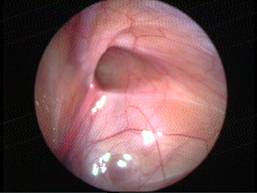

Torsion of Left Undescended Testis (Pre operative and Operative Photo)